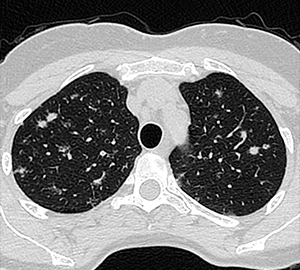

Femenina 59 años. Asintomática, Hallazgo en control anual.